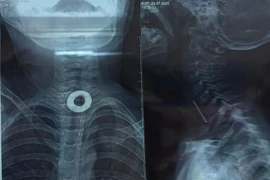

Chơi đùa, trẻ 7 tuổi nuốt phải kim loại 2cm kẹt trong thực quản

Hóc dị vật nhỏ triệu chứng đau không dữ dội nên dễ bị bỏ sót gây ra các biến chứng nguy hiểm như áp xe thực quản, thủng thực quản, vỡ áp xe, xuất huyết...